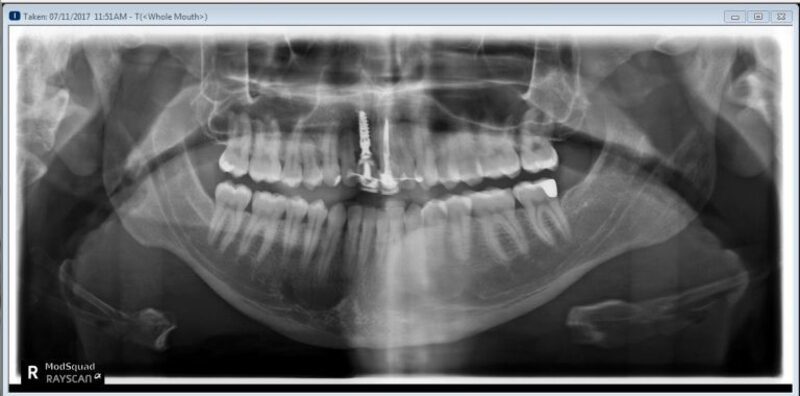

Trường hợp trụ Implant đặt sai vị trí

Trong trường hợp trụ Implant đặt sai vị trí nhưng có ít sự sai lệch, bác sĩ có thể tháo bỏ mão răng sứ và thực hiện niềng răng như bình thường. Sau khi quá trình chỉnh nha hoàn tất, bác sĩ sẽ đặt lại mão răng sứ trên Implant. Tuy nhiên, trước khi làm lại mão răng sứ, bác sĩ cần sử dụng trụ phục hình cá nhân hóa hoặc bẻ góc để đảm bảo mão răng mới phù hợp với vị trí chính xác của răng Implant.

Trong trường hợp trụ Implant bị sai lệch quá nhiều và không thể thực hiện các biện pháp chỉnh sửa như trên, bác sĩ sẽ quyết định tháo bỏ hoàn toàn chân răng Implant. Sau đó, quy trình niềng răng được thực hiện đến khi khớp cắn đã ổn định, bác sĩ sẽ tiến hành cấy lại Implant mới nếu cần thiết.

Hình ảnh các trụ Implant đặt sai vị trí (Nguồn: Avant Dental)